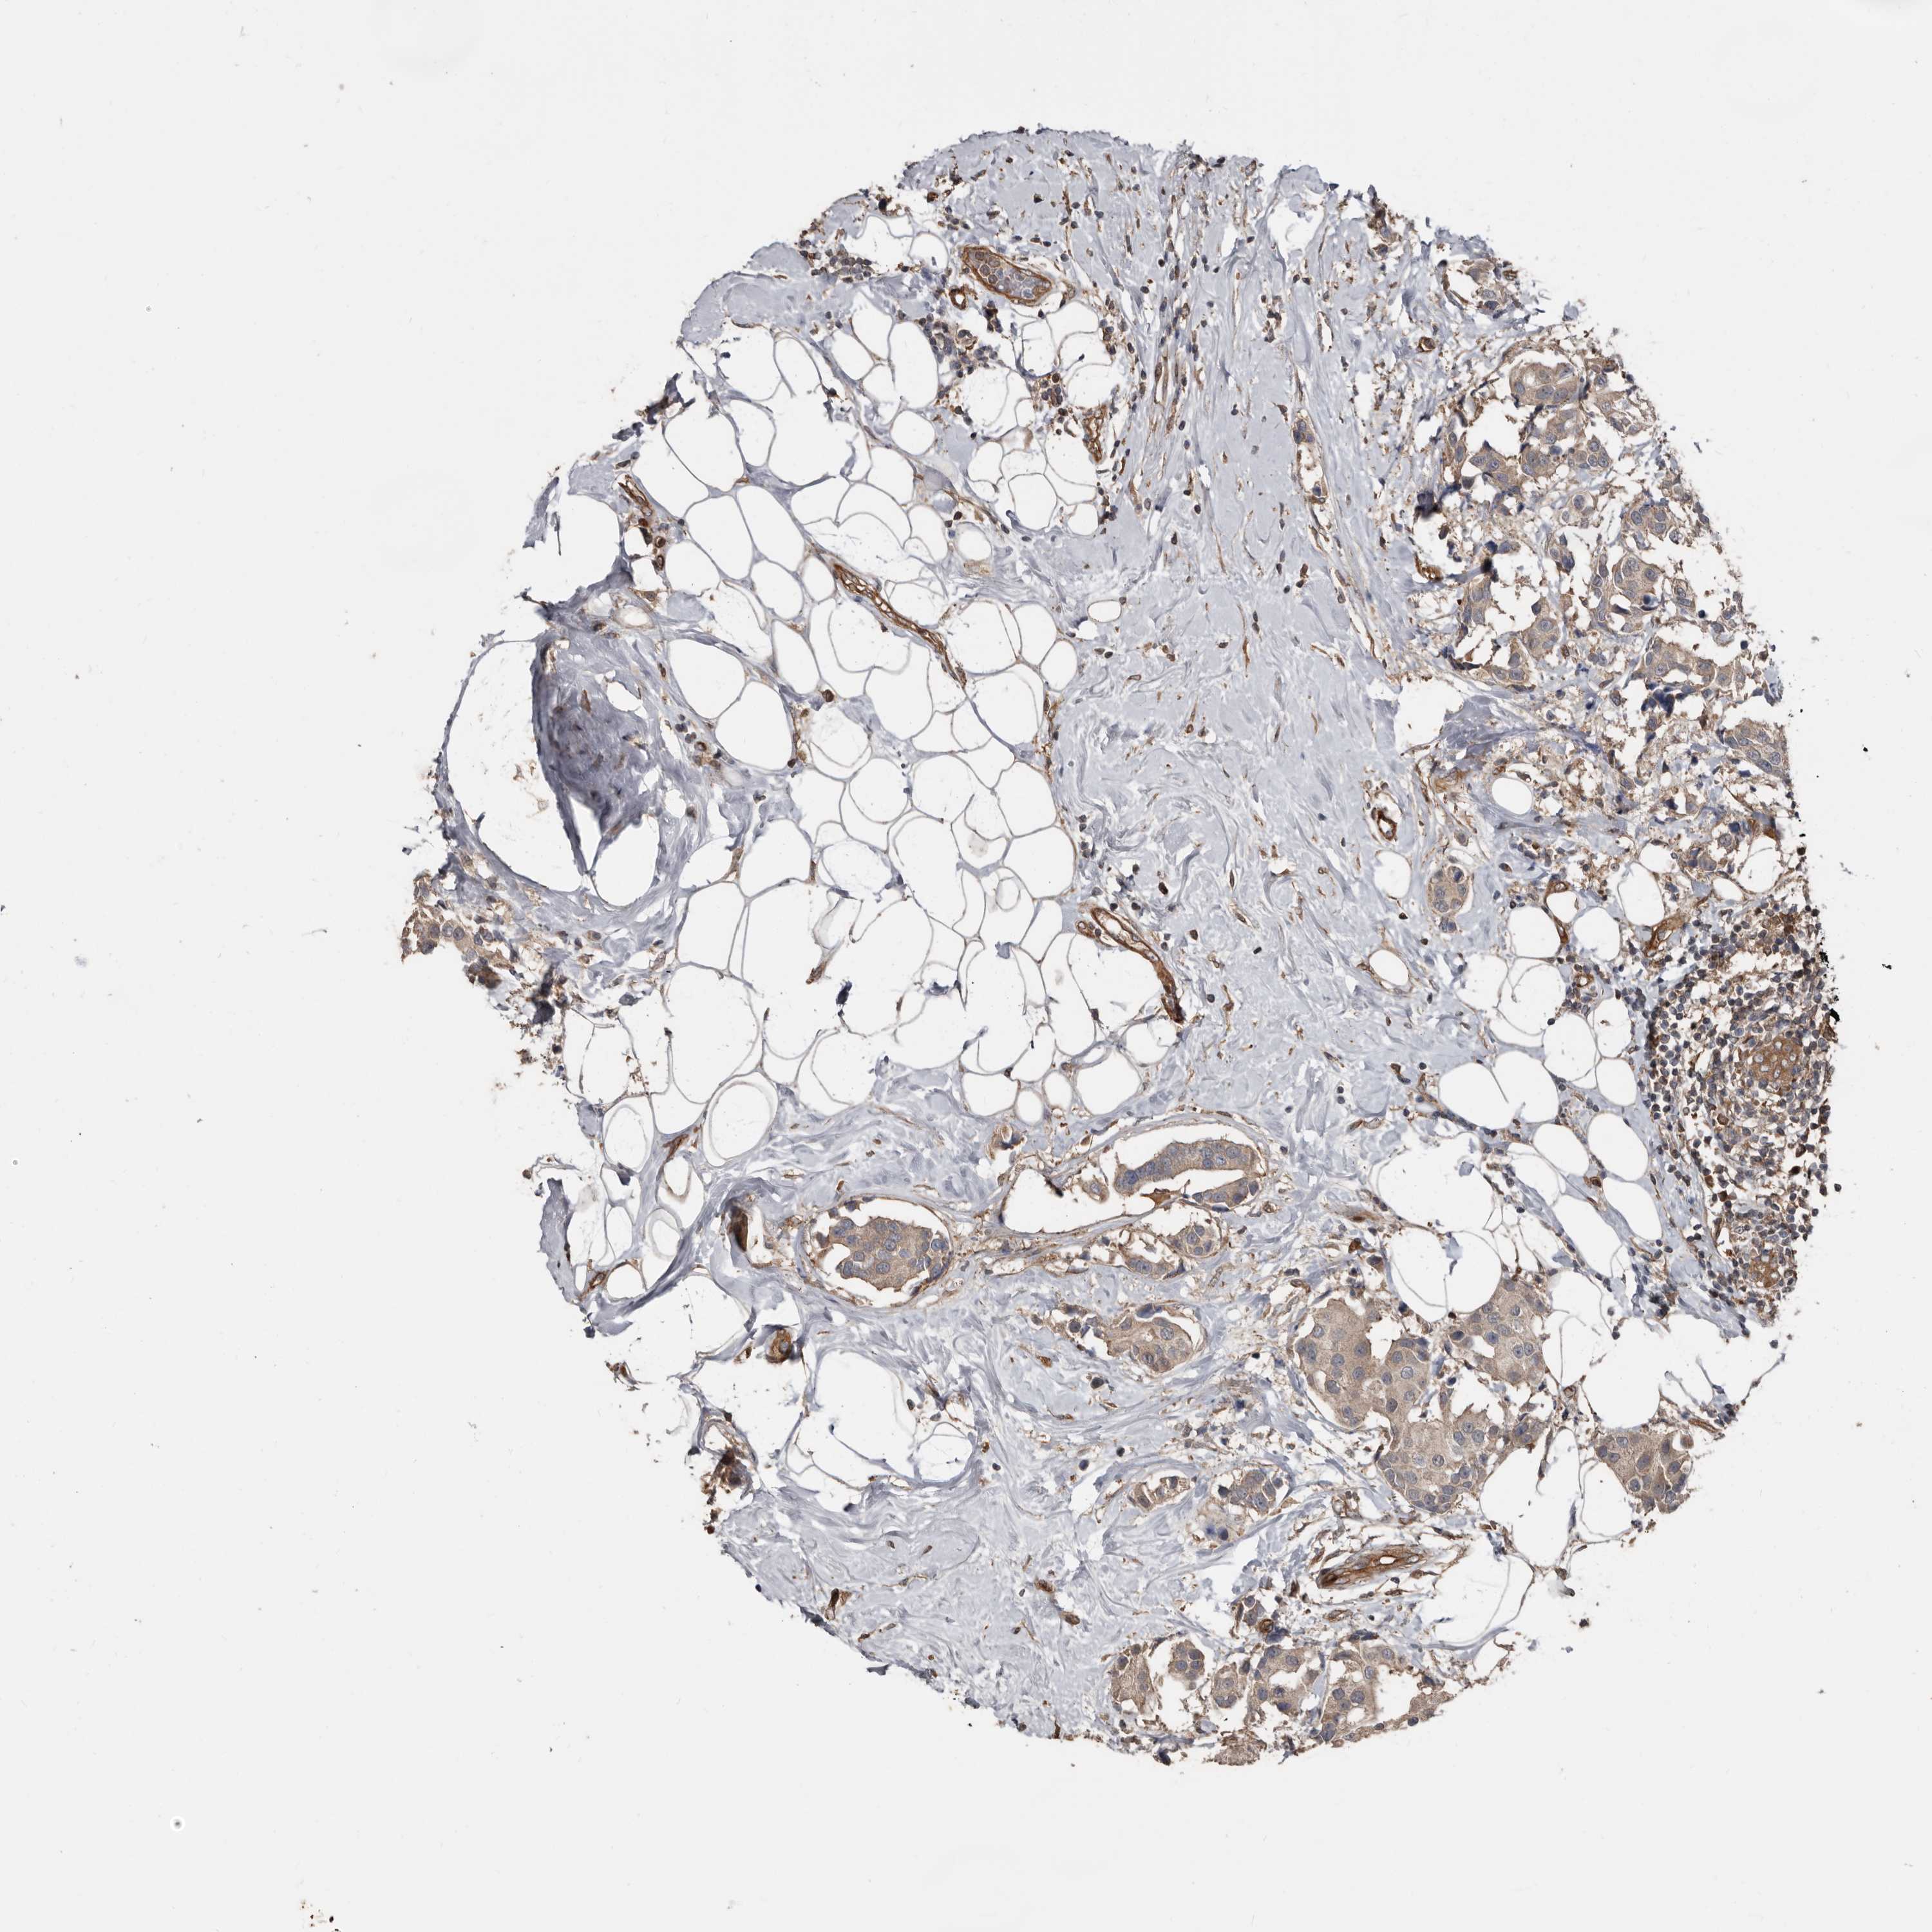

CANCER BREAST CANCER Show tissue menu

BRCA TCGA BRCA VALIDATION PROTEIN EXPRESSION